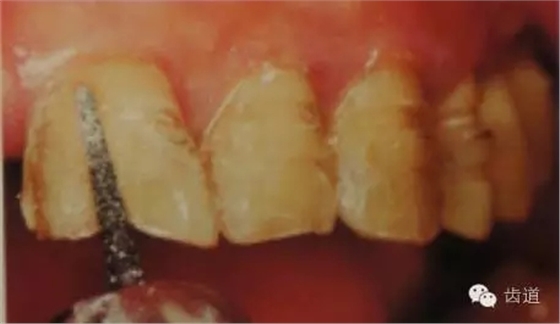

5、齦緣制備:通常瓷貼面的齦端邊緣位于齦上近齦緣處,但當(dāng)美觀要求時(shí)也可以設(shè)計(jì)在齦下0.5mm。

預(yù)備齦下邊緣之前要先排齦,之后選用圓頭錐形車針磨除牙體到所設(shè)計(jì)的邊緣位置。

1)排齦

2)制備